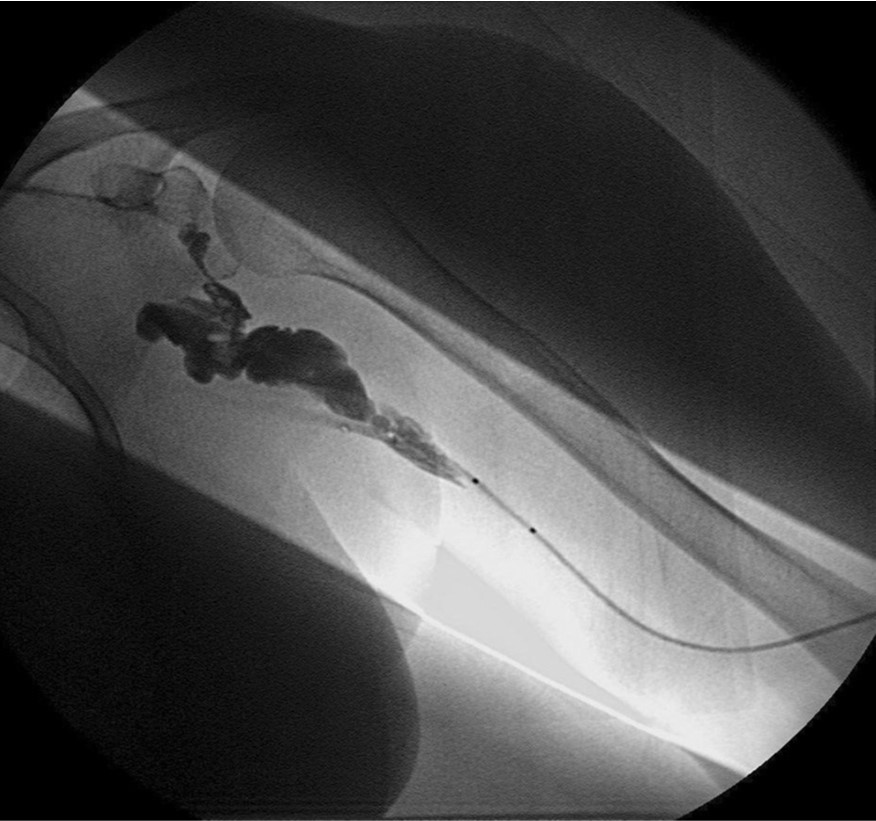

Retrograde venogram을 시행하면서 left basilic vein을 찾아 두 개의 7mm balloon(synergy, Boston, Ireland)을 사용하여 occlusion 된 vein 에 대한 Criss-Cross “double-balloon” angioplasty를 시행하였다(Fig. 6) .

Fig. 6.

Criss-Cross “double-balloon” technique in left basilic van